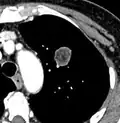

PET scan

FDG-PET study of a 71-year-old woman with a solitary pulmonary nodule (thin arrow) in the left lower lobe near the heart. The scan also revealed abnormal increased activity at the gastro-esophageal junction (thick arrow). The final diagnosis was non-Hodgkin lymphoma at both sites.

If there is an intermediate risk of malignancy, further imaging with positron emission tomography (PET scan) is appropriate (if available). It can be done simultaneously as a CT scan in the form of PET-CT. Around 95% of patients with a malignant nodule will have an abnormal PET scan, while around 78% of patients with a benign nodule will look normal on PET (this is the test sensitivity and specificity).[15] Thus, an abnormal PET scan will reliably pick up cancer, but several other types of nodules (inflammatory or infectious, for example) will also show up on a PET scan. If the nodule has a diameter of less than one centimeter, PET scans are often avoided because of an increased risk of falsely normal results.[15][16][17] Cancerous lesions usually have a high metabolism on PET, as demonstrated by their high uptake of FDG (a radioactive sugar).